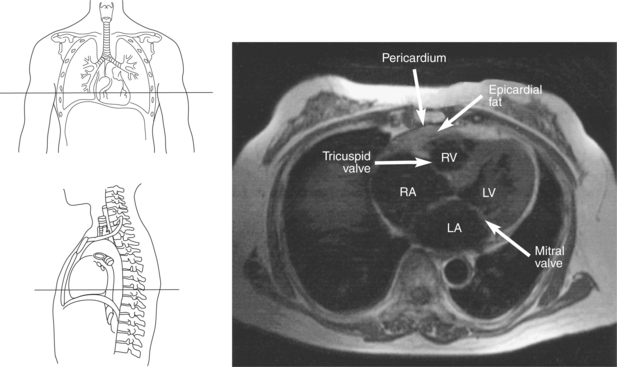

Figure 6.43 Axial, T1-weighted MR scan of left atrium.

Key: RV, Right ventricle; LV, left ventricle; LA, left atrium; RA, right atrium.

The right atrium forms the right border of the heart and receives deoxygenated blood from the body via the superior and inferior venae cavae and from the coronary sinus and cardiac veins that drain the myocardium. A small muscular embryonic appendage, the right auricle, projects upward and toward the left from the right atrium, covering the root of the aorta (Figure 6.40). The right ventricle lies on the diaphragm and comprises the largest portion of the anterior surface of the heart. It receives deoxygenated blood from the right atrium and forces it into the pulmonary trunk for conveyance to the lungs. Projecting off the inferior surface of the ventricular walls are conical-shaped projections of cardiac muscle called papillary muscles that anchor the cusps of the tricuspid valve to the right ventricle (Figure 6.39). The left atrium lies posterior to the right atrium and is the most posterior surface of the heart. It also has an embryonic appendage, the left auricle, that projects to the left of the pulmonary trunk over the superior surface of the heart. The left atrium receives oxygenated blood directly from the lungs via the four pulmonary veins (two on each side). The left ventricle forms the apex, left border, and most of the inferior surface of the heart. It receives oxygenated blood from the left atrium and pumps it into the aorta for distribution throughout the systemic circuit. The myocardium of the left ventricle is normally three times thicker than that of the right ventricle, reflecting the force necessary to pump blood to the distant sites of the systemic circulation (Figures 6.41 through 6.52). Two papillary muscles project from the ventricular walls to anchor the bicuspid valve to the ventricle (Figures 6.39 and 6.47).

The two atrioventricular valves are found at the entrances to both ventricles and function to prevent backflow of blood between the atria and ventricles during ventricular contraction. These valves have leaflets that are attached to the papillary muscles by thin cords of fibrous tissue called chordae tendineae. The right atrioventricular valve, with three leaflets, is called the tricuspid valve, and the left atrioventricular valve, with two leaflets, is called the bicuspid (mitral) valve (Figures 6.39, 6.43, 6.44, 6.47, and 6.48).

The heart is enclosed in a pericardial sac that surrounds the heart and the proximal portions of the great vessels entering and leaving the heart. The fibrous pericardium is attached to the central tendon of the diaphragm and is pierced by the inferior vena cava. The inner surface of the fibrous pericardium consists of a double-layered serous membrane termed the serous pericardium. The serous pericardial layers are the parietal layer that lines the inner surface of the fibrous pericardium and the visceral layer (epicardium) that covers the outer surface of the heart and the roots of the great vessels. Located between the two layers is a potential space (pericardial cavity) containing a thin film of serous fluid that acts as a lubricant to reduce friction to the tissues caused by heart movement. Located between the pericardium and the heart wall is a layer of epicardial fat that is typically more prominent near the venous inflow and arterial outflow of the heart (Figures 6.36 through 6.38).